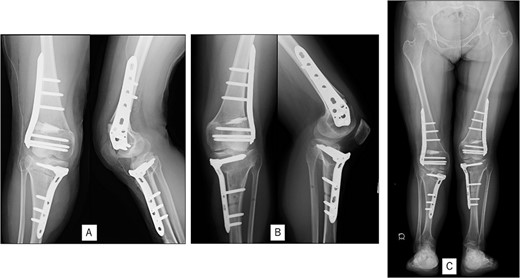

A 23-year-old woman presented with bilateral knee pain and gait abnormalities owing to marked lower extremity deformity. She was diagnosed with EVC as a child but had never been followed up by orthopedics because she was not in pain. On physical examination, marked valgus instability was observed in both knees, and the motion of both knees ranged from 10° to 135°. Radiographic examinations of both knees, including computed tomography, showed valgus deformity, lateral and anterior depression of the proximal lateral tibial plateau, and external rotation deformity of the lower leg. Patellar dislocation was observed in the right knee (Fig. 1). The radiological angles are presented in Table 1. The right knee underwent surgery first, followed by the left 10 months later. Lateral and medial skin incisions were made. Extensive lateral retinacular release, fractional lengthening of the distal lateral hamstring, and Z-lengthening of the iliotibial band were then performed. At this stage, peroneal nerve strain was identified, and decompression of the peroneal nerve was performed. Osteotomy was subsequently performed on the tibia. Closed-wedge varus and derotational osteotomy of the proximal tibia and open-wedge varus osteotomy of the distal femoral varus were performed. In addition, vastus medialis advancement was performed on the right knee, and patellar realignment was achieved in extension (Fig. 2). However, the knee showed a subluxation tendency owing to flexion of >30°; therefore, the postoperative rehabilitation plan progressed more slowly than that of the left knee. Range of motion training began on the left knee immediately after surgery without any restrictions, but on the right knee only after 3 weeks of postoperative immobilization in the extended position. However, ambulation exercise was performed on both knees with no loading for 3 weeks, then partial loading was initiated, and full loading was permitted at 8 weeks postoperatively. Early postoperative standing radiography showed residual mild valgus deformity of the lower limbs (Fig. 2, Table 2). In addition, the right knee showed patellar re-dislocation 2 months postoperatively, and the patellar deformity gradually progressed owing to the femoral implant; therefore, the patient underwent implant removal, tibial tubercle transfer, and medial patellofemoral ligament reconstruction 1.5 years after the initial surgery (Fig. 3). Six months later, she fell while walking and developed a fracture at the osteotomy of the right femur; open reduction and internal fixation were performed (Fig. 4). The remaining years passed uneventfully, and 10 years after the initial surgery, the patient still had mild valgus deformity of the lower limbs, but had no recurrence other than that experienced immediately after surgery, no complaints of knee pain, and a stable gait (Fig. 5, Table 2).

Radiography after fracture at the osteotomy of the right femur. (A) anteroposterior and lateral view immediately after fracture. (B) After open reduction and internal fixation.